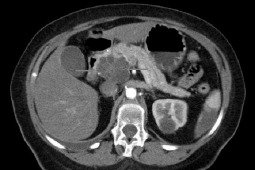

-Nowotwór trzustki należy do wysoce śmiertelnych, złośliwych nowotworów o słabych rokowaniach. Dodatkowo wykazuje wysoką oporność na chemioterapię i radioterapię - zauważa portal biotechnologia.pl .